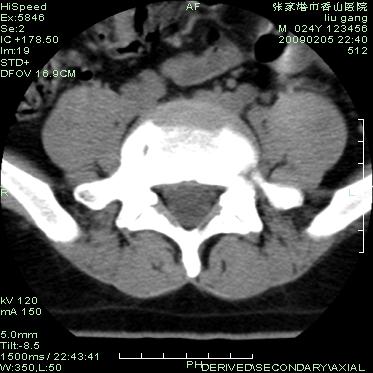

以下是引用随光逐影在2009-3-11 14:43:00的发言:[br]平片:l3、4、5及s1前上缘见类似“切角征”。[br]ct扫描:腰椎多个节段椎间盘向椎体内(椎体前部)突出。